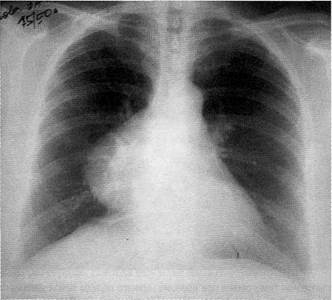

Рентгеновские снимки тератомы средостения: Диагностика и лечение

Раздел: Фотоэссе